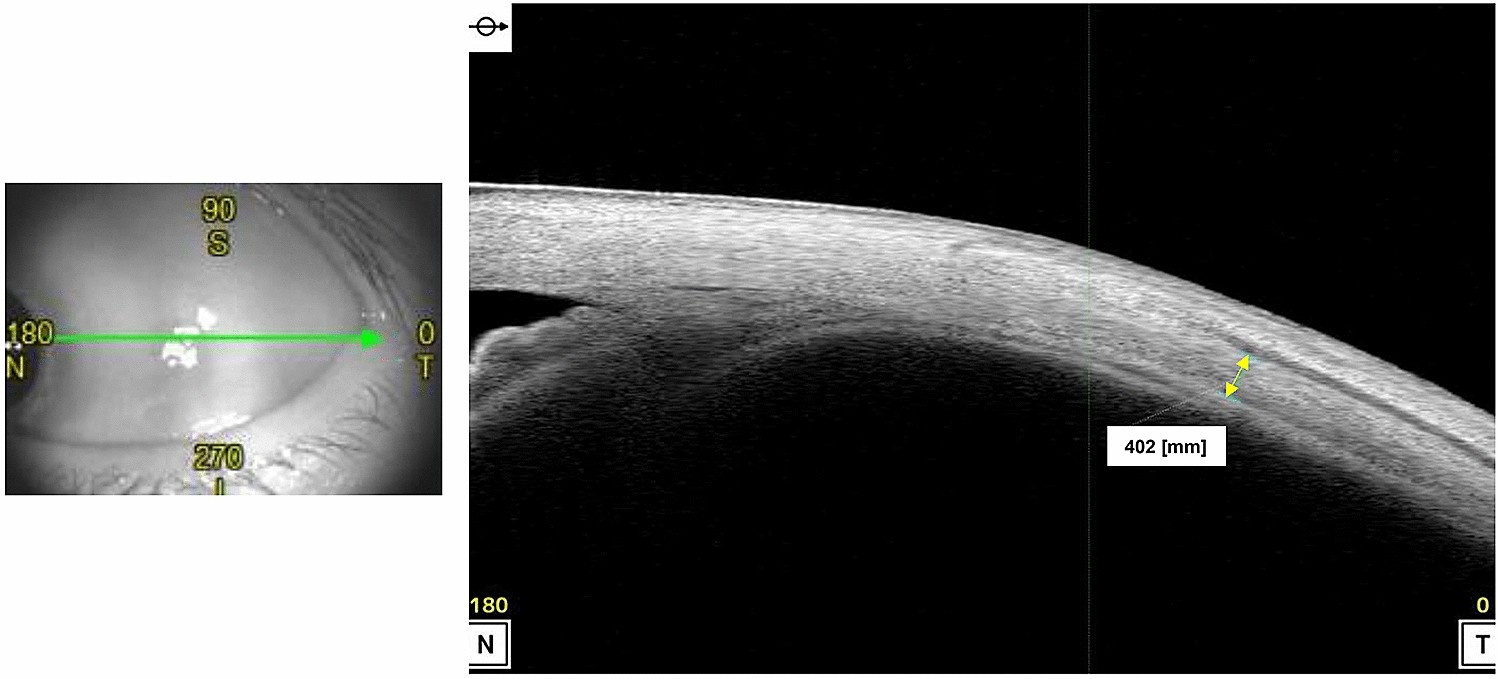

Figure 5

Method of obtaining image of temporal sclera and measuring scleral thickness using anterior segment optical coherence tomography.